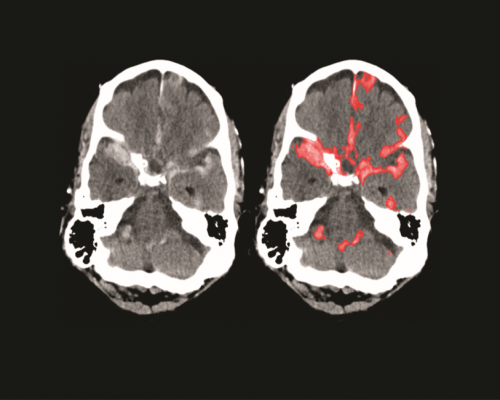

New Delhi, September 3, 2025 – Road accidents and traumatic injuries often cause internal brain hemorrhage, which, if undetected in time, can lead to death. Addressing this urgent medical challenge, Indian scientists and engineers have developed a handheld, portable device that can detect brain hemorrhage within two minutes, eliminating the immediate need for a CT scan.

The breakthrough device uses non-invasive near-infrared spectroscopy technology. By scanning the patient’s head, it can instantly detect whether bleeding has occurred inside the brain. Trials conducted at Ahmedabad Civil Hospital on more than 70 patients showed 100% accuracy in detecting hemorrhage.